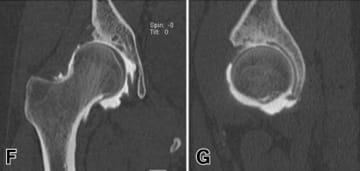

Periacetabular osteotomy (PAO)

Described by Ganz in 1988, this has become the gold-standard in hip-preserving surgery for DDH in North America and it is seeing increasing use in France [5] Ganz R, Klaue K, Vinh TS, Mast JW. A new periacetabular osteotomy for the treatment of hip dysplasias. Technique and preliminary results. Clin Orthop Relat Res. 1988 Jul;(232):26–36. https://doi.org/10.1097/00003086-198807000-00006 (Figure 5).

This is a surgical strategy for acetabular reorientation that preserves the posterior column, maintaining the stability of the pelvis and allowing the surgeon to avoid the reorientation challenges involving the sacrospinous and sacrotuberous ligaments.

The fragment is mobilised directly to achieve the rotation and then fixed with screws (4.5mm or 3.5mm), positioned from the iliac crest to the mobilised fragment without penetrating the joint.

Rotational acetabular osteotomy (RAO) is a technique initially described by Ninomiya and Tagawa in 1984, and it is another surgical strategy for acetabular reorientation, this time practised almost exclusively in Eastern Asia, and mainly in Japan [6] Yasunaga Y, Ochi M, Yamasaki T, Shoji T, Izumi S. Rotational Acetabular Osteotomy for Pre- and Early Osteoarthritis Secondary to Dysplasia Provides Durable Results at 20 Years. Clin Orthop. 2016 Oct;474(10):2145–53. https://doi.org/10.1007/s11999-016-4854-8. It differs from PAO, with a spherical incision that does not disrupt the structure of the pelvic ring. A modified Smith–Petersen approach is used, which offers exposure of the anterior osteotomy in the interval between sartorius and tensor fasciae latae, as well as posteriorly, in a similar way to the Kocher–Langenbeck approach. The osteotomy is performed first with a motorised burr then with curved osteotomes under fluoroscopic guidance, avoiding releasing any fragments of acetabulum that are too fine (risk of necrosis) or creating a gap within the joint. The fragment is mobilised using a hook, fixed with screws and the osteotomy site is repaired with a cancellous bone graft (Figure 5). Another technique making use of a trochanteric osteotomy to improve visibility has been described.